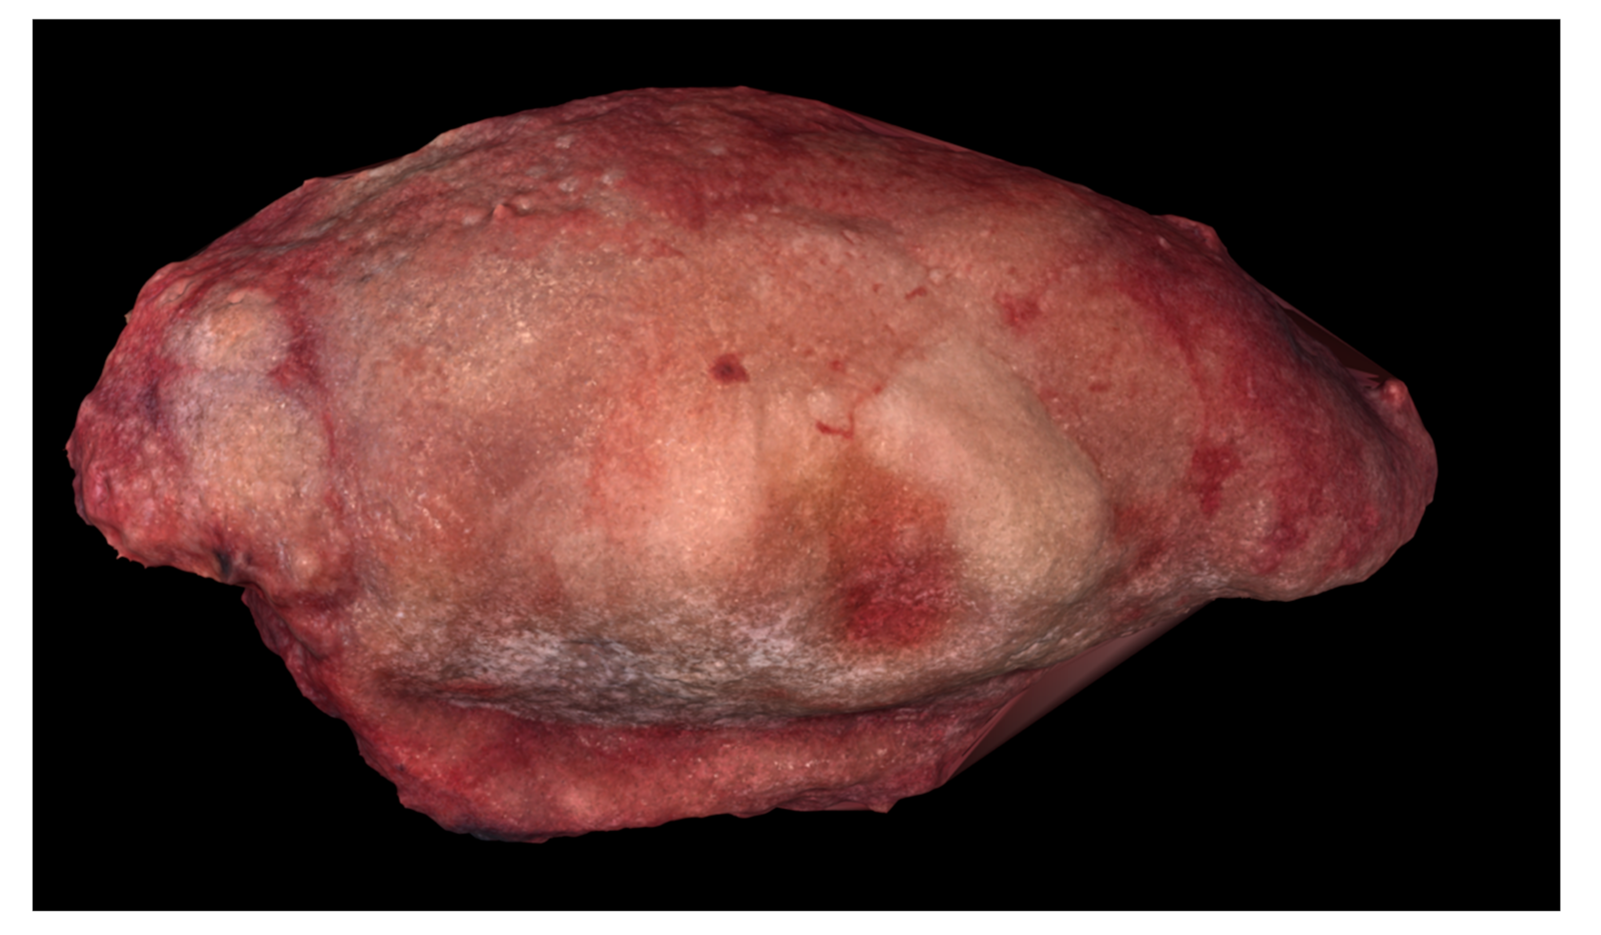

Table 1 summarizes the main parameters from the reconstruction. “Photographs taken” refers to the number of smartphone photographs, taken from various orientations, introduced into the photogrammetry software. Aligned photographs were able to be utilized during the computation and construction of the digital 3D model (Figure 4, Figure 5 and Figure 6). Processing time gives an approximate total time span required by the alignment, dense cloud creation, and meshing steps.

Figure 4.

Digital 3D model of Case 1 using Meshlab.

Digital and physical models of the surgical resection block were produced within one week of the operation. The 3D model dimensions were scaled up from the true dimensions of the resection block due to the small size of each tumor. Enlarging the dimensions of the model allowed for improved visualization of surface topography and anatomical details. For Case 1, the model produced by binder jetting conveyed more information than the material extrusion model because of the added color texture made possible by binder jetting (Figure 7 and Figure 8). Using material extrusion, the model was made of simple ABS-like white polymer with less detail.